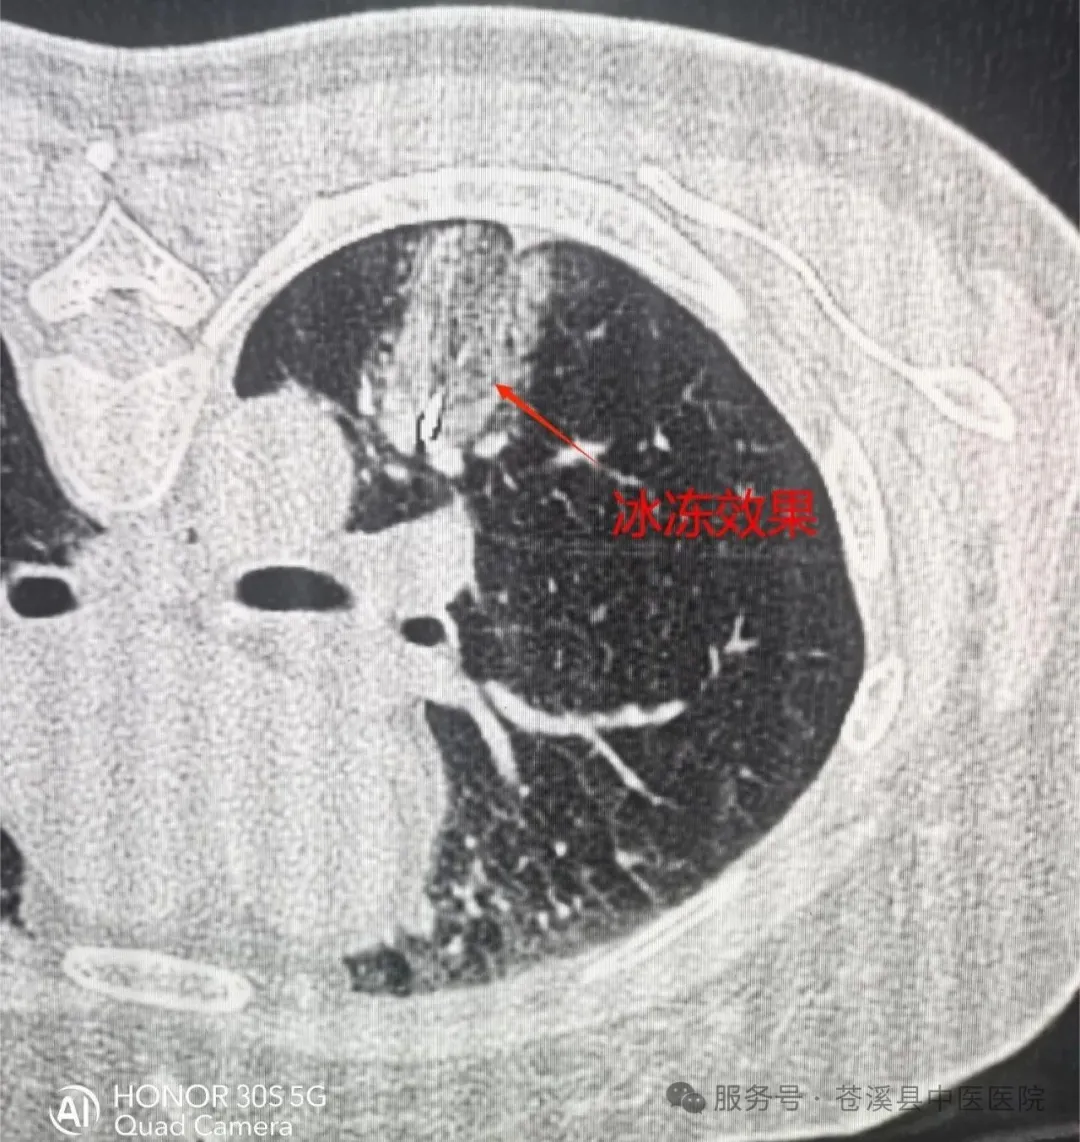

【新技术】苍溪县中医医院成功实施全县首例肺病损氩氦刀冷冻术

近日,苍溪县中医医院放射介入医学科成功完成全县首例肺病损氩氦刀冷冻术,患者术后恢复良好,第二天即可下床活动。

氩氦刀冷冻术是通过氩气作用,将病灶整体降温至约-160℃,随后氦气启动,迅速升温至45℃左右,完成数次“冰火两重天”的极致转换。治疗过程中,肿瘤细胞遭受剧烈冲击,迅速破裂、崩解。同时,肿瘤血管也因栓塞而坏死,无法再为肿瘤提供“滋养”,从而实现肿瘤的有效物理杀灭与控制。冻死的“肿瘤细胞”相当于肿瘤原位疫苗,刺激免疫系统发生免疫反应,达到抑制肿瘤生长的作用,起到“隔山打牛”的效果。